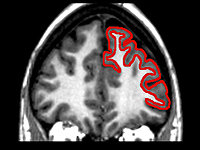

Shown in red, the frontal lobe is the home of the central processing unit in the brain. This red highlighted area decreases in volume as we age. This region helps the brain decide which tasks to focus on and when to disregard those that don’t matter.

Researchers can actually see the brain struggle when people attempt to multitask. It becomes an over-stimulating process for us mentally, and our frontal lobe simply gets worn out.